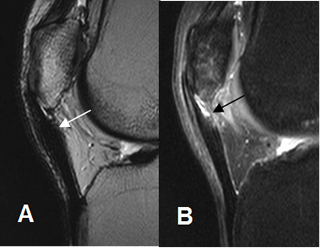

Fig 151. Ruptura parcial del tendón patelar.

A: RM sagital en T2 y B: RM sagital en STIR. Engrosamiento en el origen del tendón patelar, por inflamación crónica. Presenta interrupción de algunas fibras en su parte posterior, por ruptura parcial.